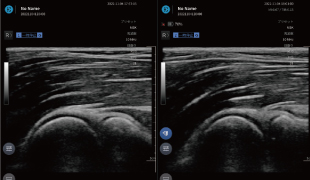

2画面機能

左右にエコー画像を並べて表示することが可能。健側・患側のリアルタイムな比較はもちろん、過去のエコー画像を表示して現在の画像と比較することによる治療の評価も可能です。